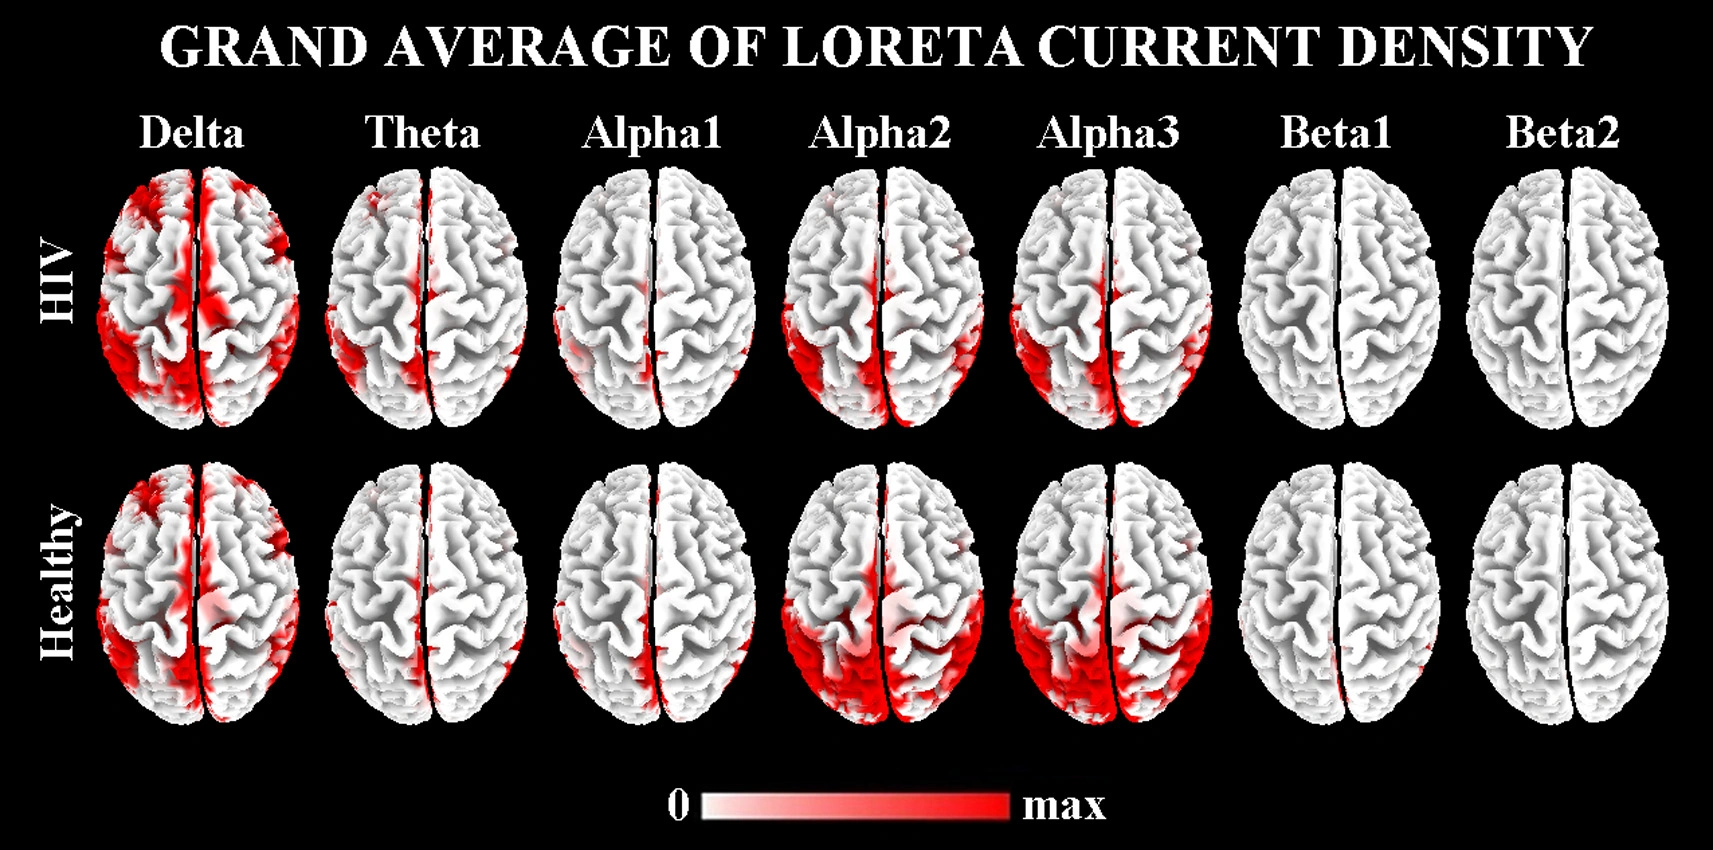

Sorgenti Corticali Anomale dei Ritmi EEG a Riposo, in Soggetti HIV Positivi, al Trattamento Naïve

Lo studio propone un metodo basato sullo Z-score per individuare anomalie EEG nei soggetti HIV positivi non trattati, mostrando una correlazione tra alterazioni corticali, peggioramento cognitivo, riduzione dei CD4 e aumento della carica virale.

Una Terapia Personalizzata per l’HIV – Pubblicazione Avanti!

Lo studio propone un metodo basato sull’analisi dell’attività cerebrale tramite EEG e tecniche di elaborazione avanzata per monitorare gli effetti dell’HIV sul sistema nervoso centrale. L’approccio consente di valutare l’impatto delle terapie antiretrovirali e di orientare trattamenti sempre più personalizzati per ogni paziente.